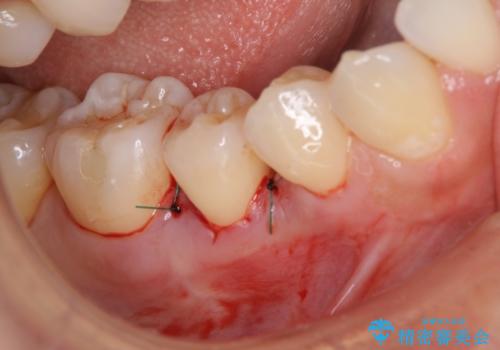

患者様は、他院で右下の歯を抜歯かもと言われました。全体の歯周病はなく、右下の1歯だけ骨が極端に減少していました(初診時歯周ポケット7mm。通常は3mm以下。)。その歯だけ咬合が強いことが原因と考えられたため、咬合を弱くする処置と減少した骨を再生する処置が必要になりました。

骨の再生治療手術をして10か月経過観察をしたのち、骨を平坦化する手術を行い、治療終了となりました。

・手術後はしばらくワイヤー等で固定する必要があります。